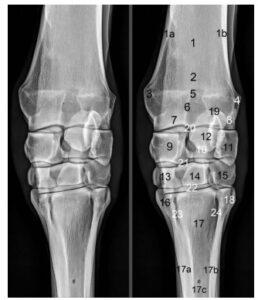

Image from Denoix, J.M. Essentials in Clinical Anatomy of the Equine Locomotor System.

9 – radial carpal bone; 10 – intermediate carpal bone; 11 – ulnar carpal bone; 13 – second carpal bone; 14 – third carpal bone; 15 – fourth carpal bone; 16 – second metacarpal bone; 17 – third metacarpal bone; 18 – fourth metacarpal bone. [25]